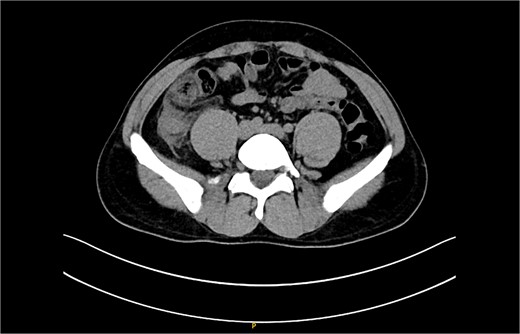

The non-contrast CT scan revealed a retrocecal appendix measuring 11 mm in diameter, with periappendiceal fluid and fat smudging, and reactive thickening of the cecum, indicating uncomplicated acute appendicitis. The patient was admitted to the surgical department and scheduled for a laparoscopic appendectomy (Figs 2 and 3).

CT scan picture with an axial view showing acute inflamed appendix with peri-appendicular fat smudging, confirming the radiological finding of acute appendicitis.